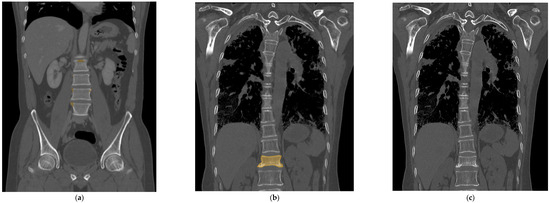

Figure 3.

As a case of false positives, the trained deep learning model color-mapped areas suspected of having fractures, but in reality, these did not have any fractures (a). However, these false positive results have a tendency to be found in the high attenuated cortex showing marginal osteophytes of the vertebra or normal endplates. In this case of a false negative, the fractured vertebra segment confirmed on the MRI was colored and trained (b), but the deep learning model could not recall a fractured segment when there was no checkered pixel (c). It appeared only as a subtle and narrow condensation zone on the CT, making it challenging to suspect a fracture even on the actual raw CT image.